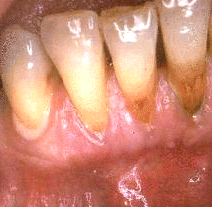

Mujer de 64 años de edad con  enfermedad periodontal severa en los dientes anteroinferiores. Al sondaje de la bolsa periodontal presentó una profundidad de  5-8 mm. En el  examen inicial al sondaje suave  presentó  flujo de pus en el margen gingival. La imagen ilustra un síntoma prominente de la enfermedad periodontal severa.